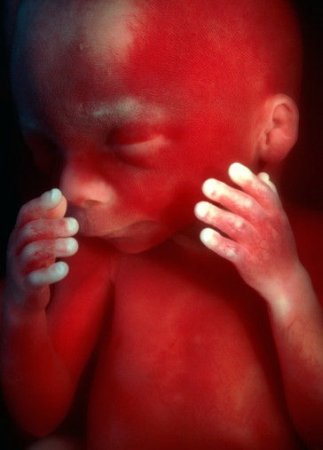

Девятый месяц, 33-36 неделя

36 неделя беременности… Еще совсем немного, и свершится долгожданное и незабываемое для женщины таинство – встреча с ее уже таким любимым малышом. «Совсем немного»… Сколько же это – совсем немного? – ближе к родам может задаться вопросом мамочка, совсем запутавшись в подсчетах. Что же происходит с плодом?

На девятом месяце беременности у малыша исчезает пушок, до этого покрывающий всё его тельце. Нарастает слой подкожного жира, цвет кожи выравнивается, приобретая красивый розоватый оттенок.

К концу 36 недели беременности ребенок занимает постоянное положение в плодном яйце, обычно – головой вниз. У малыша дозревают легкие и печень, сердцебиение составляет 120-140 ударов в минуту. Весит малыш в среднем 2800 грамм, а его рост составляет около 46 см. И хотя развитие малыша и укрепление его организма всё еще продолжаются, он уже может появиться на свет без особой опасности для жизни.